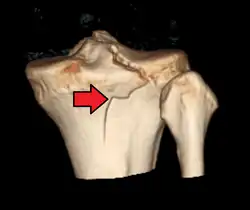

3D reconstruction of a CT image of a tibial plateau fracture